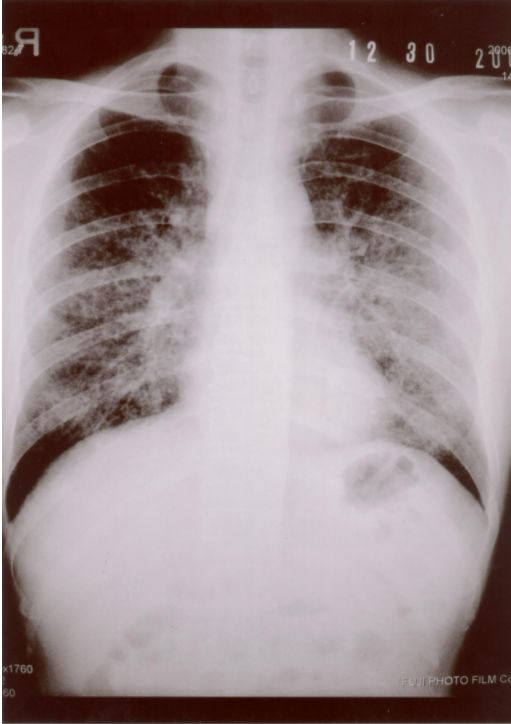

13. 39歲男性有多重性伴侶,因持續發燒及體重減輕3公斤,而且逐漸感到呼吸困難而入院,身體檢查發現口腔有白色珠菌 (Candida)感染,胸腔 X光如圖35 ,血液檢查結果: HIV Test :陽性、血液淋巴球比率: 8%、 CD3:34% 、CD4:0.2%、 CD8:36% 、CD19:4%,肺部灌洗液檢出囊胞蟲(Pneumocystis carinii),下列敘述何者為真?a. 囊胞蟲肺炎 ( Pneumocystis carinii pneumonia ) 典型表現為兩側肺門旁之浸潤,很快迅速進展成瀰漫性兩側肺部浸潤b. AIDS合併囊胞蟲肺炎患者的死亡率為單獨感染囊孢蟲肺炎者之三倍c. 所有囊胞蟲肺炎患者均需住院治療d. 大部HIV合併囊胞蟲肺炎病患的症狀均為突發性咳嗽,高燒而無呼吸困難症症狀e. Trimethoprium-Sulfamethoxazole仍為治療及預防囊蟲肺炎之首選藥物